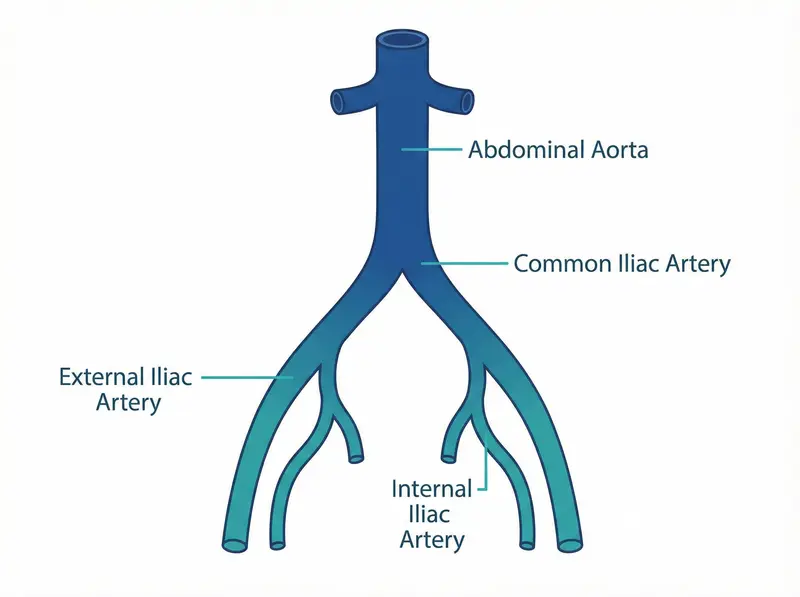

The abdominal aorta is the largest artery in the body. It runs from the heart through the chest and abdomen, supplying blood to the lower body. When the wall of the aorta weakens, it can balloon outward — a condition known as an abdominal aortic aneurysm (AAA). An aorta measuring more than 3 cm in diameter is considered dilated; above 5.5 cm it carries a significant risk of rupture.

The examination evaluates the aorta and iliac vessels using greyscale imaging and colour Doppler. The table below summarises the structures assessed and the conditions identified.

| Aortic bifurcation | Greyscale morphology; bifurcation point | Bifurcation aneurysm, plaque, stenosis |

| Common iliac arteries | Bilateral diameter; Doppler waveform | Iliac aneurysm, occlusion, stenosis |

Both common iliac arteries are measured and assessed for dilation or occlusion. The bifurcation point is examined for plaque or aneurysmal change.